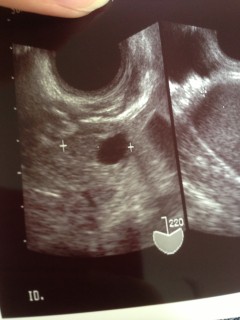

この写真をいただく診察の前日、思いっきり腰から転んでしまい 不安で不安で半泣きで病院に駆け込みました。 赤ちゃんは無事とのことで、10.9mmの胎嚢が確認できました。 私は中隔子宮という子宮奇形なのですが(胎嚢すぐ左の黒い部分が子宮の真ん中にある壁) 1人目は右の部屋でしたが、今回の赤ちゃんは左の部屋にいるそうです。

念のため、安静にという指示が出ました。 1人目の妊娠まで8年かかり、2人目は諦めかけていたのですが 来てくれました。 お姉ちゃんのお世話で、なかなか安静にするのが難しいですが、 できるだけ言い聞かせて2週間後の検診まで過ごしたいと思います。